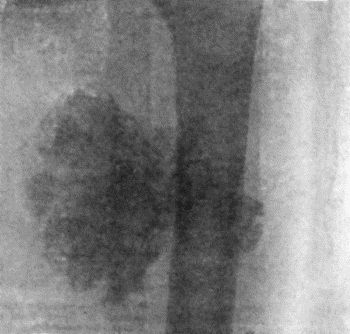

| 78. | Mass of Tuberculous Glands removed from Axilla | 333 |